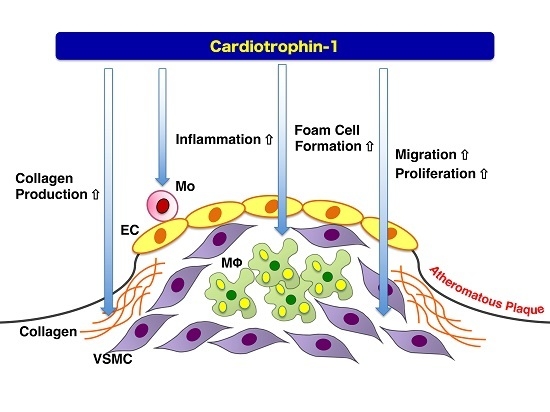

6. Atheroprone Effects of CT-1

- Konii, H.; Sato, K.; Kikuchi, S.; Okiyama, H.; Watanabe, R.; Hasegawa, A.; Yamamoto, K.; Itoh, F.; Hirano, T.; Watanabe, T. Stimulatory effects of cardiotrophin 1 on atherosclerosis. Hypertension 2013, 62, 942–950. [Google Scholar] [CrossRef] [PubMed]